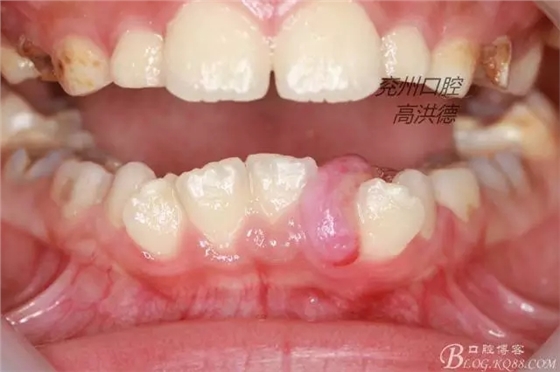

患兒孔xx,性別男,7歲,其母在3月前發(fā)現(xiàn)患兒下頜前牙處有約花生米大小的腫物,曾在其他醫(yī)院就診,建議患兒口服抗生素,不見好轉(zhuǎn),3月來呈漸進性生長,來診,孩子正面照。

檢查見;患兒發(fā)育正常,神態(tài)自如,開口度正常,混合牙列,腫物位于31,32之間,32受腫物擠壓影響遠(yuǎn)中傾斜。

診斷:牙齦纖維瘤